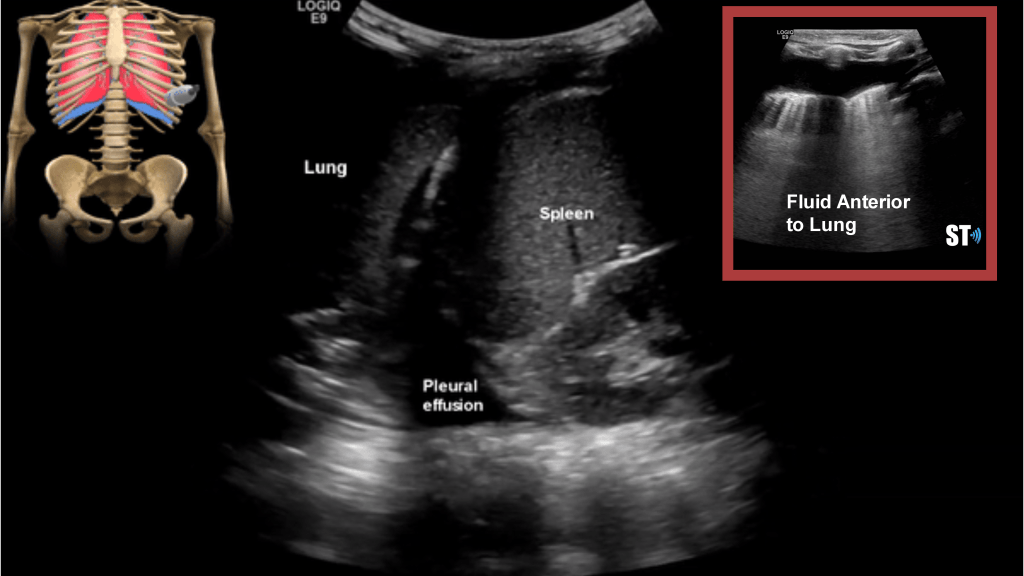

Another study on ultrasound findings found these types of lesions:

- rough discontinuous pleural line

- subplueral consolidation

- visible b-lines

- pleural effusion

- poor blood flow on consolidated lung tissue with color doppler

Potential ultrasound findings: (note these are non Covid-19 patients)

Pleural Effusion